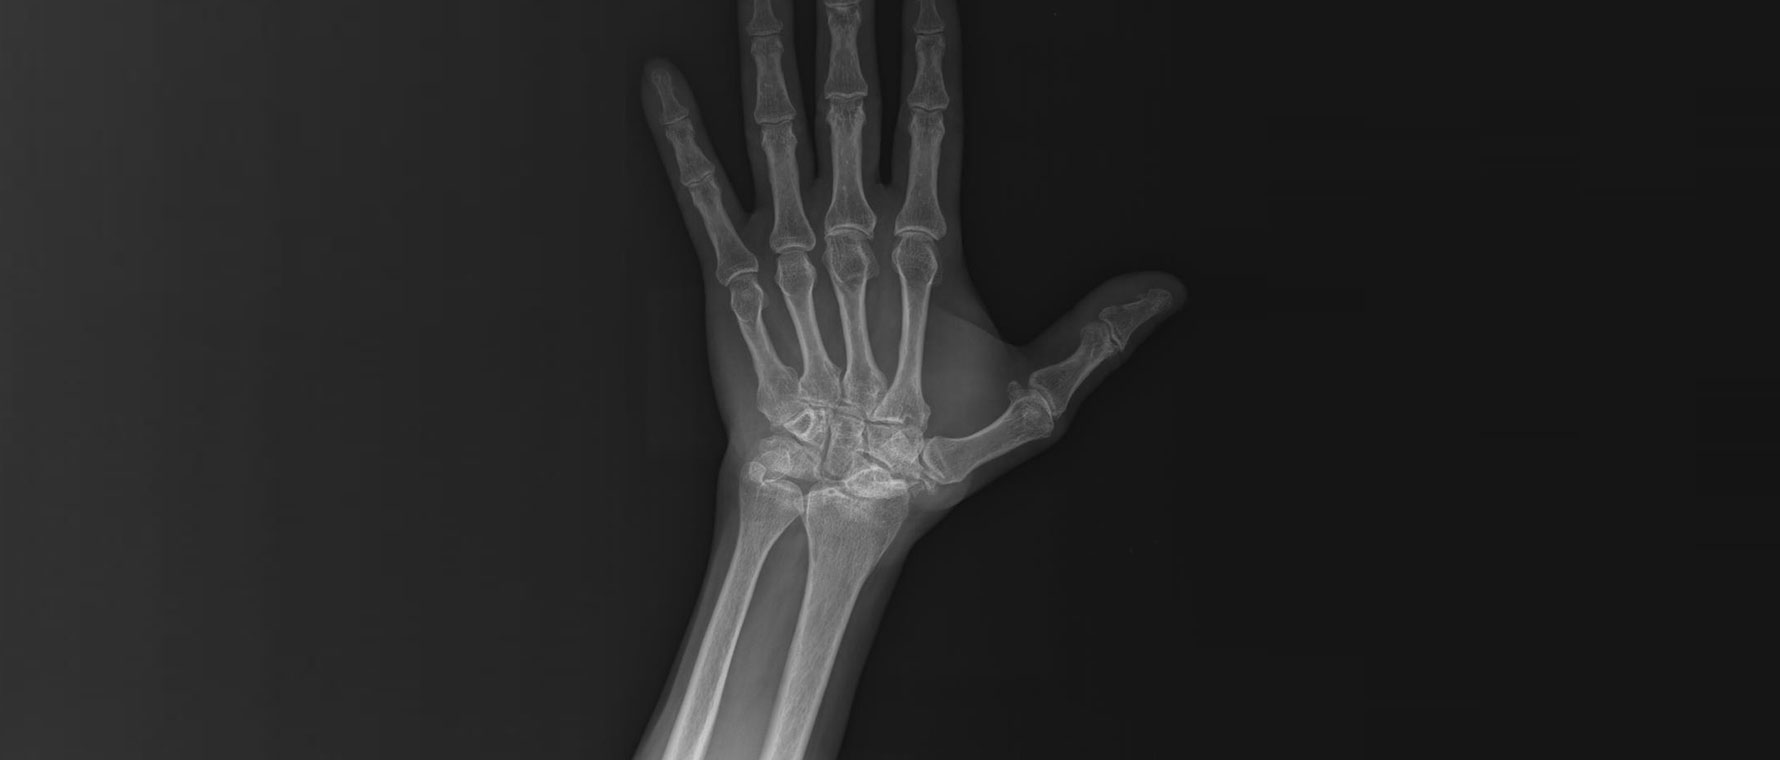

Skafoid Kaynamama Sebebiyle El Bileği Kireçlenmesi (SNAC)

SNAC, skafoid kemiği kırığının kaynamaması sonucu el bileğinde zamanla gelişen kireçlenmedir. Bu durumda bilekte ağrı, hareket kısıtlılığı ve güç kaybı ortaya çıkar. Şikâyetler yıllar içinde artabilir ve yapılacak tedaviler de değişebilir. Tanı muayene ve görüntüleme yöntemleriyle konur. Tedavide hastalığın evresine göre farklı yaklaşımlar uygulanır. Erken evrede skafoid kemiğini kaynatma amaçlı açık ameliyatlara ek radius kemiğinin kireçlenen yüzü tıraşlanabilir. Daha ileri evrelerde ise kısıtlı el bilek kemik kaynaştırma ameliyatı olan dört köşe füzyon ameliyatı ya da el bilek kemiklerinin skafoid kemiğini içeren sıra kemiklerin çıkarılması işlemi olan proksimal sıra karpektomiler uygulanabilir. Çok ileri vakalarda ise el bileği kemiklerinin hepsinin kaynaştırma ameliyatı yapılır.

Skafolunat Bağ Yırtığı Sebepli El Bileği Kireçlenmesi (Slac)

SLAC, el bileğinde skafoid ve lunat kemikleri arasındaki bağın yırtılması sonrası gelişen ilerleyici kireçlenmedir. Başlangıçta bilekte ağrı ve güçsüzlük görülür, zamanla hareket kısıtlılığı artar. Günlük işler zorlaşabilir. Tanı muayene ve röntgen ile konur. Tedavi, hastalığın evresine ve hastanın ihtiyaçlarına göre planlanır. Erken dönemde konservatif yöntemler uygulanabilir. İleri evrelerde cerrahi ile ağrıyı azaltan ve hareketi koruyan girişimler tercih edilir. Bunlar arasında, bazı el bilek kemiklerinin kaynaştırıldığı dört köşe füzyon ameliyatı veya skafoid kemiğiyle birlikte üst sıradaki kemiklerin çıkarıldığı proksimal sıra karpektomi yer alır. Çok ileri ve yaygın kireçlenme durumlarında ise, el bileğini tamamen sabitleyen total el bileği füzyonu tercih edilebilir.